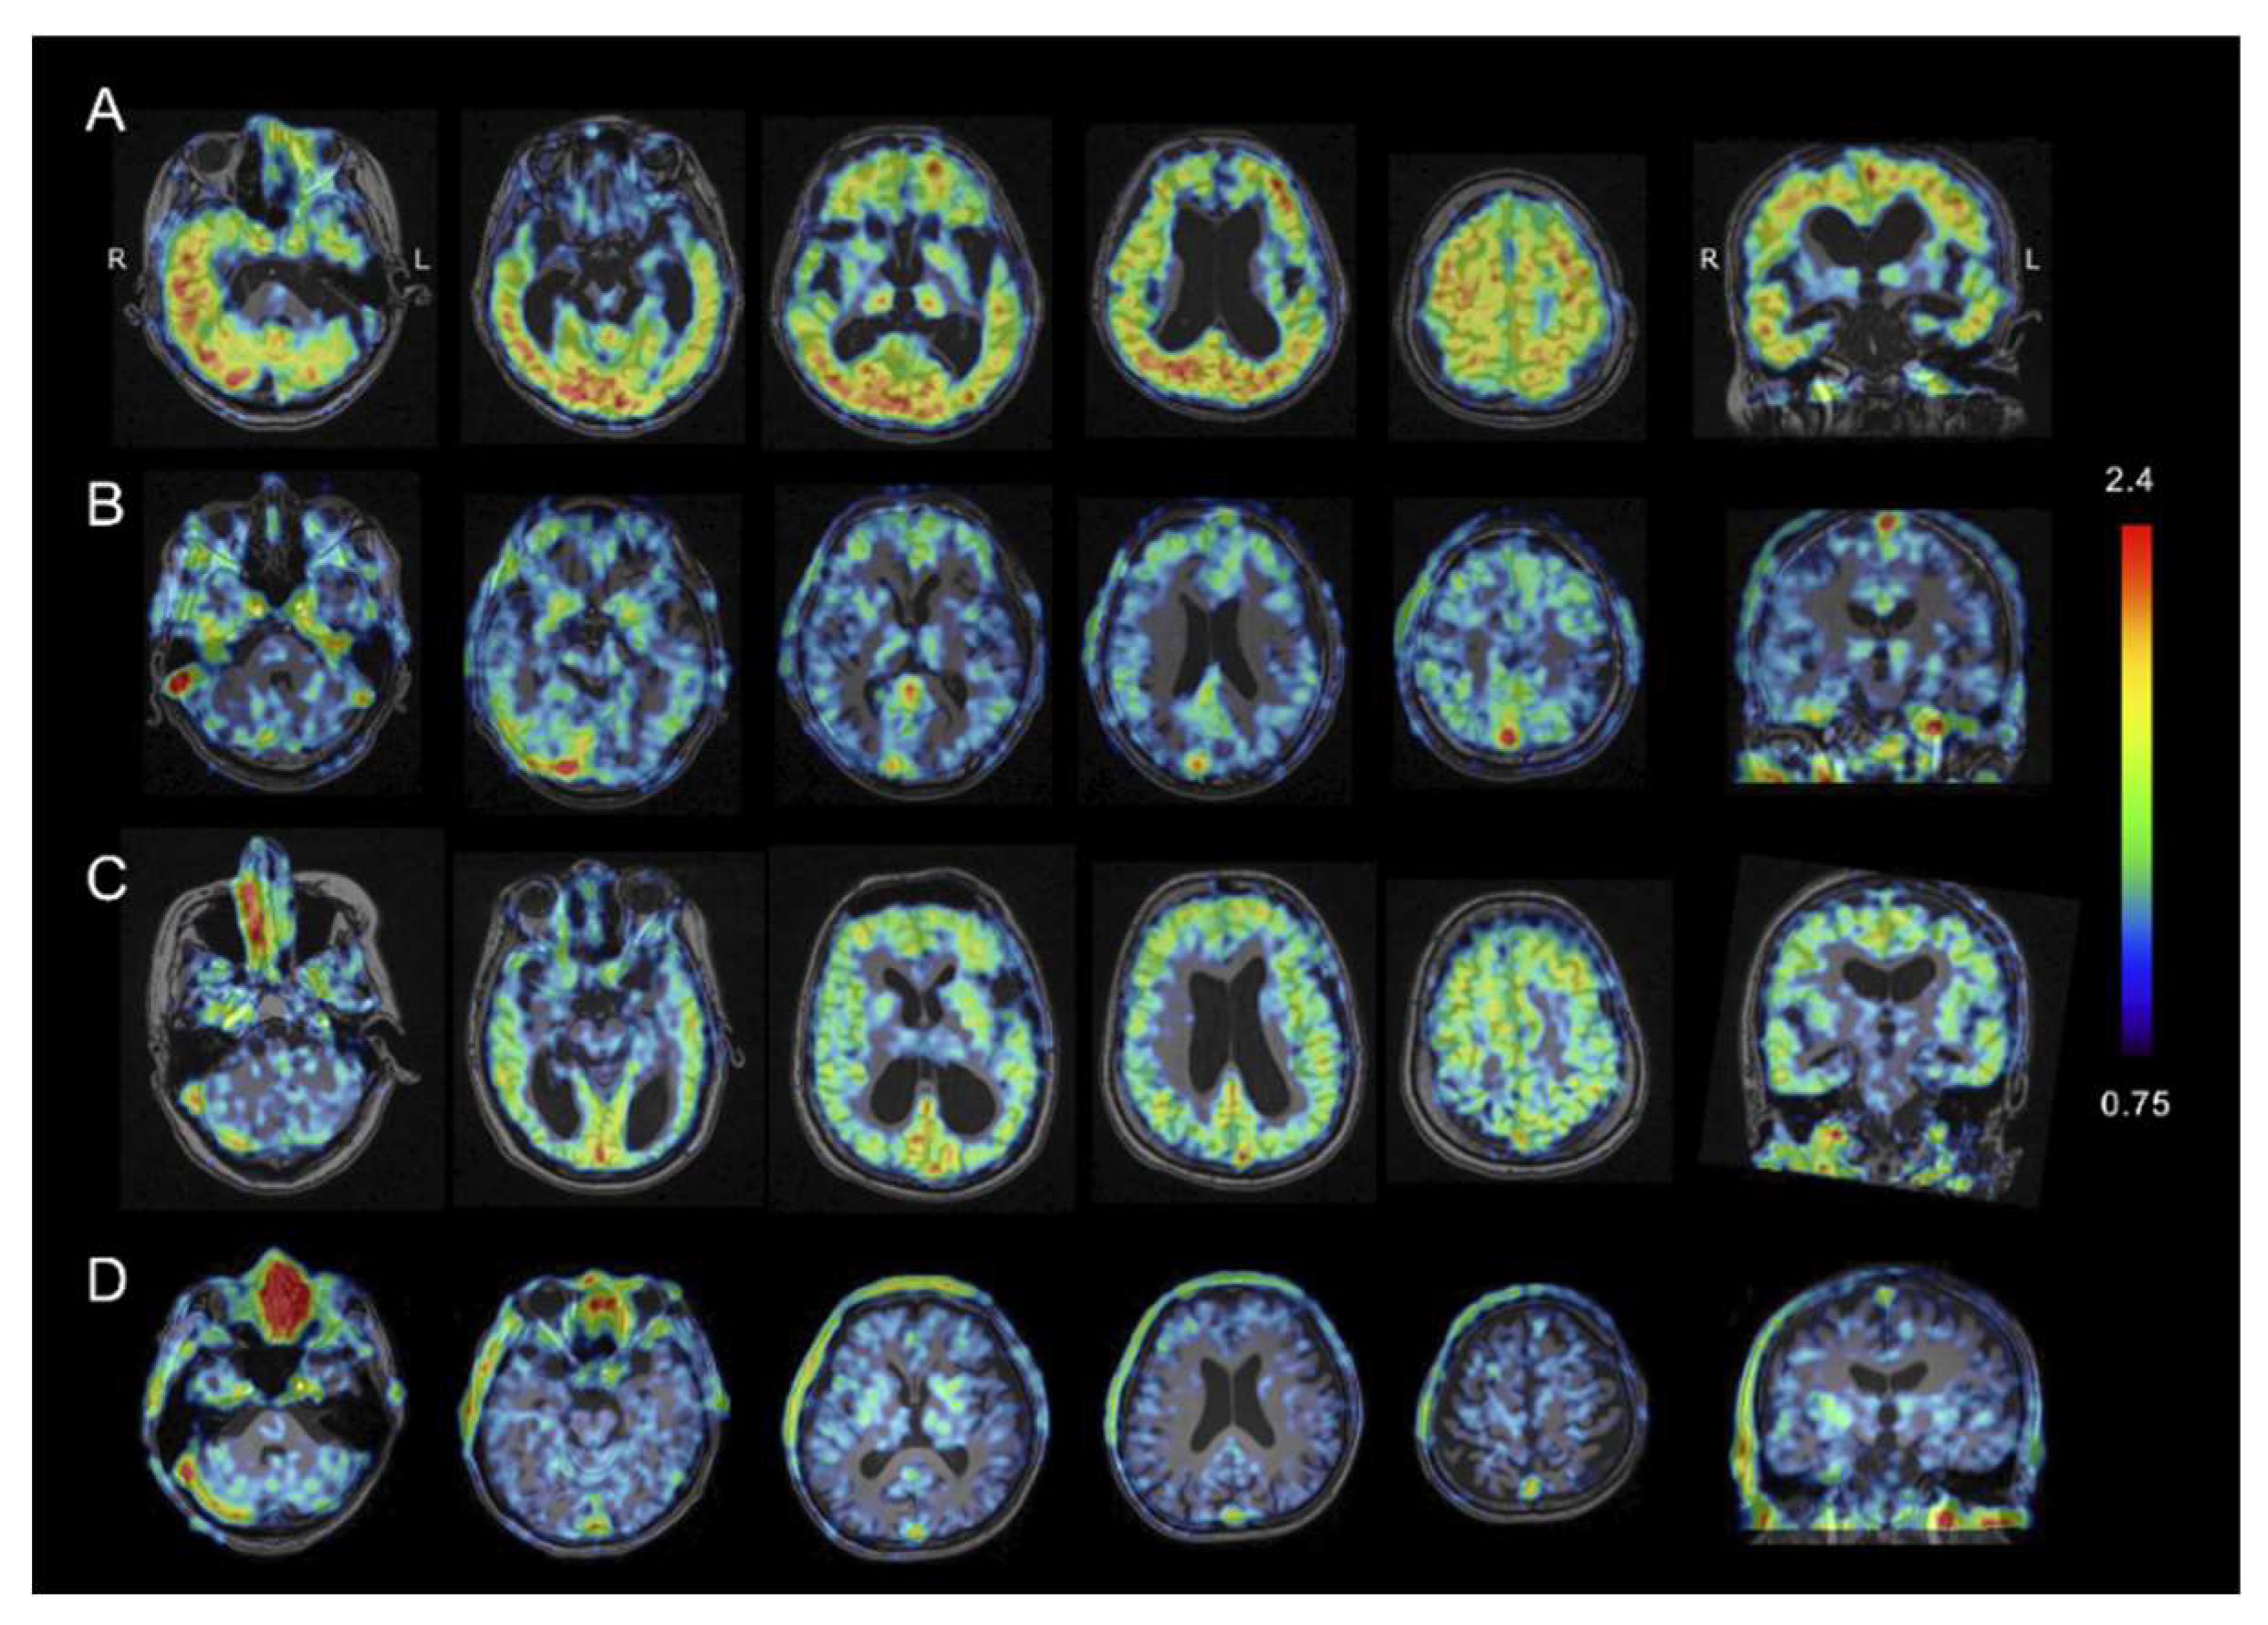

2.3. Tau PET Imaging